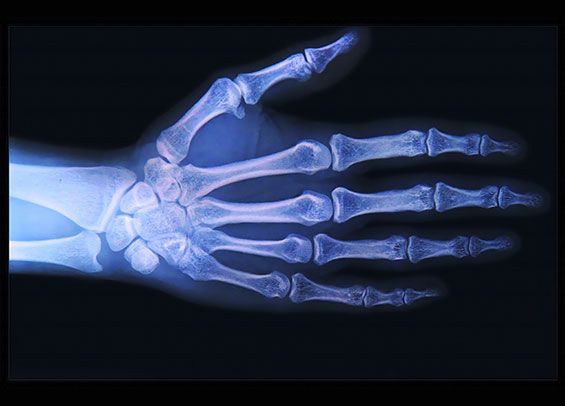

En el consultorio del Dr. Juan Fco. López Garza usted cuenta con la asistencia de un médico reumatólogo en Tampico, Tamaulipas especialista en el tratamiento de artritis reumatoide, tratamiento de osteoporosis y tratamiento de dolor de lumbalgia, así como para otros múltiples padecimientos.

está capacitado para diagnosticar a sus pacientes, dar seguimiento y control adecuado al problema que le causa una deficiencia en su sistema óseo en busca de eliminar el dolor de huesos y malestares que estos conllevan.

tratamiento de artritis reumatoide y atención especializada en reumatología es empleada tecnología de punta y los tratamientos más eficaces para disminuir dolencias y síntomas, de esta forma usted tendrá una mejor calidad de vida.